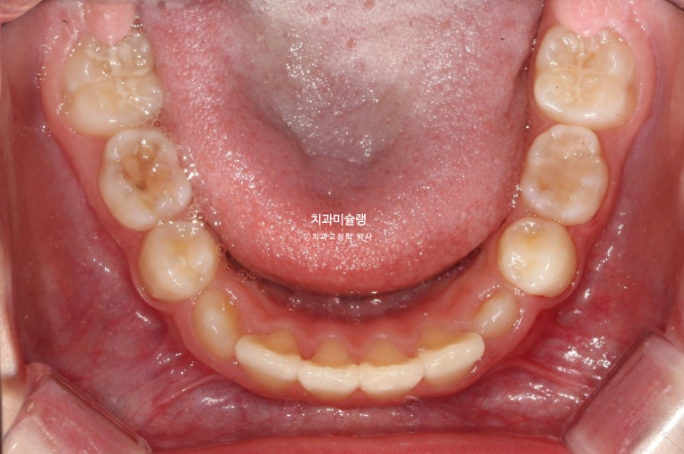

두번째 추가장치 16개를 모두 낀 후 치료를 종료했습니다.

25.08

유지장치는 과개교합 재발을 방지하기 위해 교합판이 들어간 유지장치를 잘때만 낍니다.

송곳니는 잘 올라오고 있습니다.

23.10~25.08